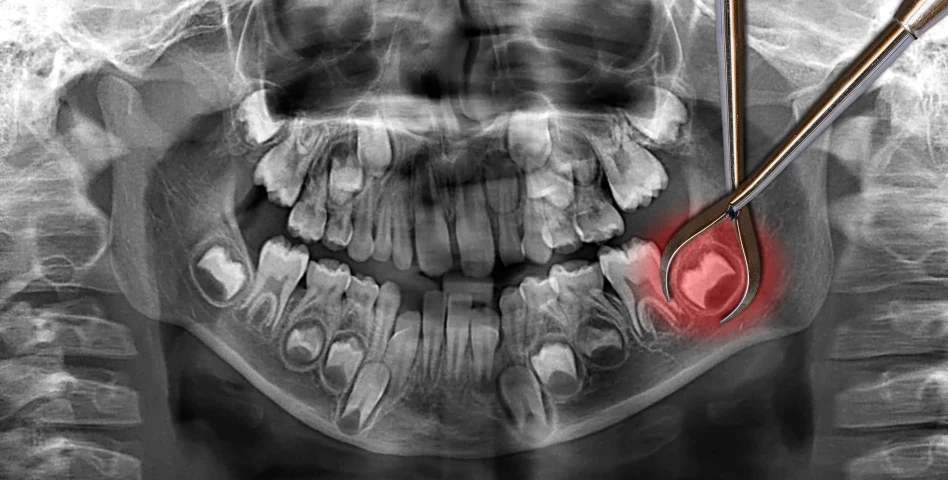

La plupart des patients, sauf contre-indications médicales sévères. Un bilan préalable (scanner, examens médicaux) est indispensable.